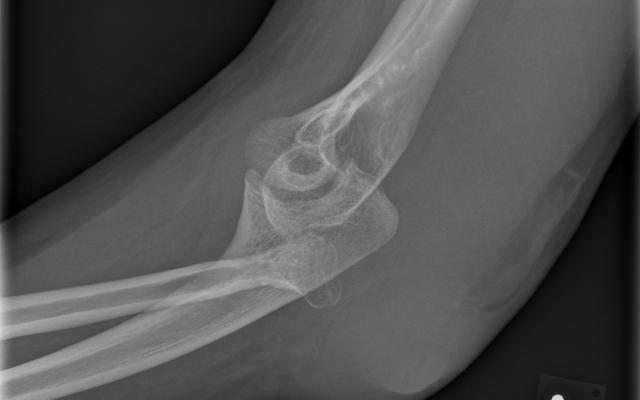

Een 24-jarige vrouw bezocht de Spoedeisende Hulp wegens een persisterend pijnlijke elleboog. De elleboog was tevens gezwollen en in functie beperkt. Patiënte had de klachten 2 weken geleden ontwikkeld na een direct trauma van de elleboog. Haar voorgeschiedenis vermeldde het Ehlers-Danlos-syndroom, waarvoor zij onder controle was in ons ziekenhuis. Lichamelijk onderzoek toonde een fors hematoom aan de dorsolaterale zijde van de elleboog met drukpijn ter plaatse (figuur a). De functie van de elleboog was nagenoeg opgeheven. Röntgenopnamen van de elleboog lieten een radiuskopluxatie zien met een congruente impressie van het capitellum humeri ter hoogte van de geluxeerde radiuskop (figuur…